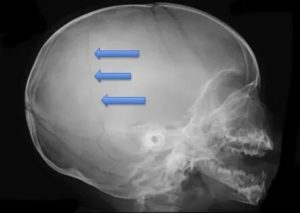

Далее доктор направляет больного на процедуру рентгенографии, которая выполняется в двух проекциях. Если травма является серьезной, то при диагностике тело не меняет своего положения, а передвигается только трубка рентгеновского аппарата.

Для постановки точного диагноза и составления прогноза выздоровления ребенку проводят рентгенологическое исследование. Краниография позволяет получить четкое изображение, но качественно расшифровать его сможет только опытный врач.

Важно не спутать трещины с сосудистой сеткой и черепными швами. Особенно тяжело отличить трещины, когда они переходят с теменной кости на лобную или затылочную области. Линия разлома имеет черный цвет. Она прямая и узкая без каких либо разветвлений.

При этом сосуды и швы имеют более светлый цвет.

Диагностика перелома теменного сегмента осуществляется с помощью рентгенографического аппарата. Снимок делается в двух проекциях: прямой и боковой.